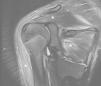

Se presenta el caso de una adolescente de 12 años, previamente sana y sin antecedente traumático, valorada en nuestro servicio de urgencias por cuadro de malestar general y fiebre hasta 39°C de 2 días de evolución. Asociaba dolor cervical que se había iniciado el día del ingreso, habiendo recibido fisioterapia por sospecha de tortícolis sin mejoría completa. En la exploración no se observó foco para la fiebre, y se constató una contractura cervical izquierda. La analítica de sangre presentaba leucocitosis con neutrofilia y elevación de reactantes de fase aguda con creatinfofoscinasa (CPK) normal (tabla 1). Se obtuvo cultivo de sangre. La radiografía de tórax fue normal. Se ingresó para observación sin antibióticos dada la afectación del estado general y el dolor. En planta persistió el cuadro febril y el dolor musculoesquelético referido progresó focalizándose a nivel del área escapular izquierda, con impotencia funcional para elevar el hombro. A las 72 h del ingreso se comunicó el crecimiento de un bacilo gramnegativo en el hemocultivo recogido al ingreso. Dada la ausencia de mejoría clínica y con los datos recibidos se inició cefotaxima intravenosa en espera de identificación del microorganismo, que posteriormente se caracterizó como Moraxella osloensis (M. osloensis, sensible a ceftriaxona, cefuroxima y ciprofloxacino). Con la sospecha de proceso osteomuscular de origen infeccioso se hizo estudio de extensión. La valoración ORL descartó participación respiratoria. Se practicó resonancia magnética (RM) de columna cervical y hombro izquierdo, apreciándose importante edema en trapecio y deltoides, sin colección purulenta, sin afectación ósea y con derrame reactivo en la articulación (fig. 1). Se quedó afebril a las 24 h del inicio del antibiótico. Progresivamente fue mejorando el cuadro, con recuperación de la funcionalidad de la articulación, desaparición del dolor y descenso de parámetros inflamatorios hasta su normalización (tabla 1) durante el ingreso. Se mantuvo tratamiento intravenoso durante 8 días completando posteriormente 3 semanas de cefuroxima axetilo en domicilio.